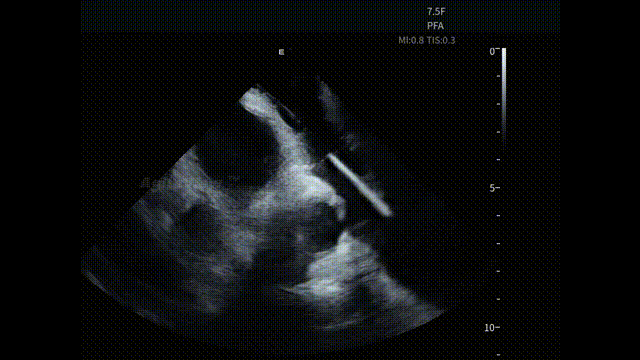

▶【术后评估:超声影像闭环,安全性确认】

手术结束前,术者操作AgileView™ ICE导管跨瓣再次对心包区域进行系统扫查,确认术后未见异常积液变化,为整台手术形成完整的安全影像闭环。

术后心包

在 ICE 实时影像的持续引导下,整台消融手术流程顺利完成。术中患者耐受良好,生命体征保持平稳,各关键操作节点均在清晰、可确认的心内超声影像基础上推进。